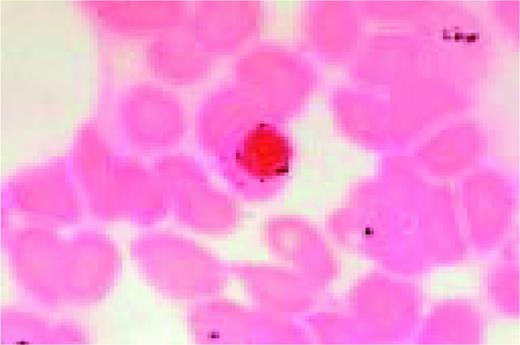

Bernard-Soulier syndrome. High-oil magnification view of a patient with the Bernard-Soulier syndrome. A typical giant platelet is seen in the center of the field.FIG87

Slide MG6